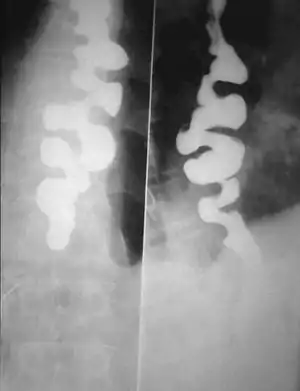

Corkscrew appearance of the esophagus.

Several radiographic findings are suggestive of DES, such as a "corkscrew esophagus" or "rosary bead esophagus" appearance on barium swallow x-ray, although these findings are not unique to DES.[2]